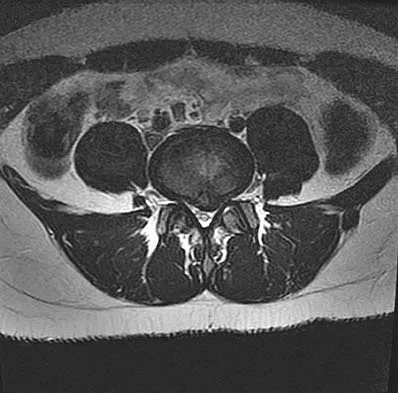

Figures 61a and 61b show the CT and MRI scans of a 40-year-old man who has hip pain. He undergoes total hip arthroplasty and curettage and cementation of the lesion as shown in Figure 61c. Histopathologic photomicrographs of the curettage specimen are shown in Figures 61d and 61e. What is the best course of treatment?

Explanation

The definitive surgery would be removal of the entire resection bed, and in this case of dedifferentiated chondrosarcoma, a hemipelvectomy was performed. The MRI and CT scans show an aggressive cartilage lesion. The histology, representative of a dedifferentiated chondrosarcoma, shows a bimorphic low-grade cartilage lesion with high-grade spindle cell sarcoma. The cartilage lesion is usually an enchondroma or low-grade chondrosarcoma. The dedifferentiated portion is typically a malignant fibrous histocytoma, osteosarcoma, or fibrosarcoma. Weber KL, Pring ME, Sim FH: Treatment and outcome of recurrent pelvic chondrosarcoma. Clin Orthop Relat Res 2002;397:19-28.